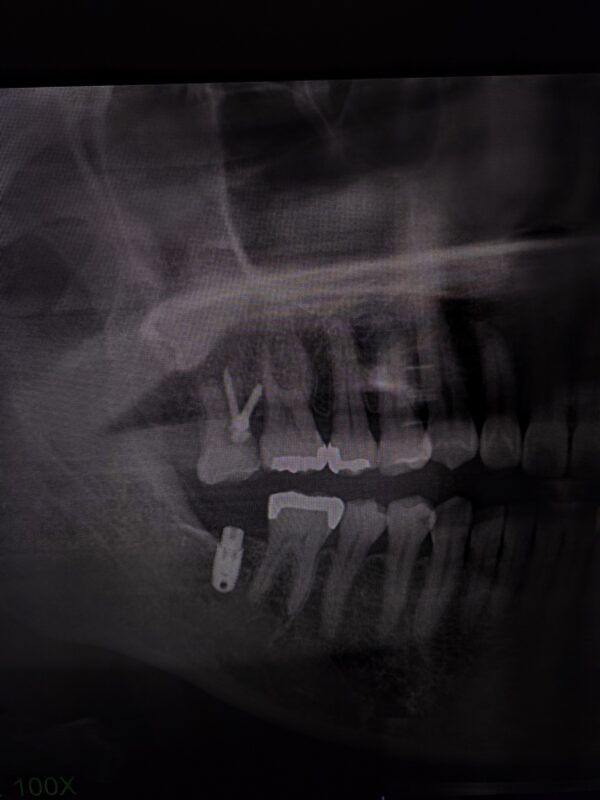

歯を抜いたままにすると 噛み合う相手を失った 写真のレントゲンのように 歯は動きます。

これを戻すには 矯正で 押しこむ方法しかありません。

やっと 下にインプラントの歯のスペースができました

押し込むのに半年以上かかりました。

もう少し押し込みたいので もうしばらく頑張ってもらわないといけません。